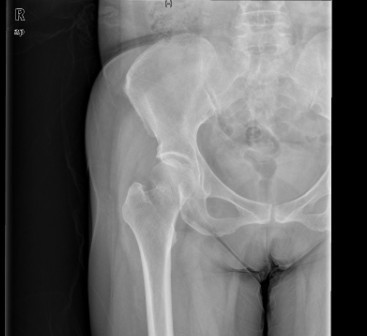

患者女,61岁,因“摔伤致右髋关节疼痛、活动受限9小时”入院。患者于入院前9小时行走时不慎摔倒,右侧肢体着地,当即感右髋关节及右大腿上段疼痛,活动受限,不能自行站立,受伤时及伤后无昏迷,无恶心、呕吐,无心累、气促,无腰痛及肉眼血尿。因休息后无缓解,急诊到当地医院行骨盆平片提示“右股骨颈骨折”,未做任何治疗,患者为求进一步治疗,遂急诊来我院,急诊以“右股骨颈骨折”收入住院。

查体:右髋关节、右大腿皮肤完整性好,右下肢轻度外旋。右腹股沟中点压痛明显,右股骨无明显压痛,未扪及明显骨擦感。右髋关节主被动活动受限。右下肢较左下肢短缩1cm。 辅查:院外X片右股骨颈骨折。

诊断:1、右股骨颈骨折(Garden III);2、骨质疏松症 治疗:择期手术